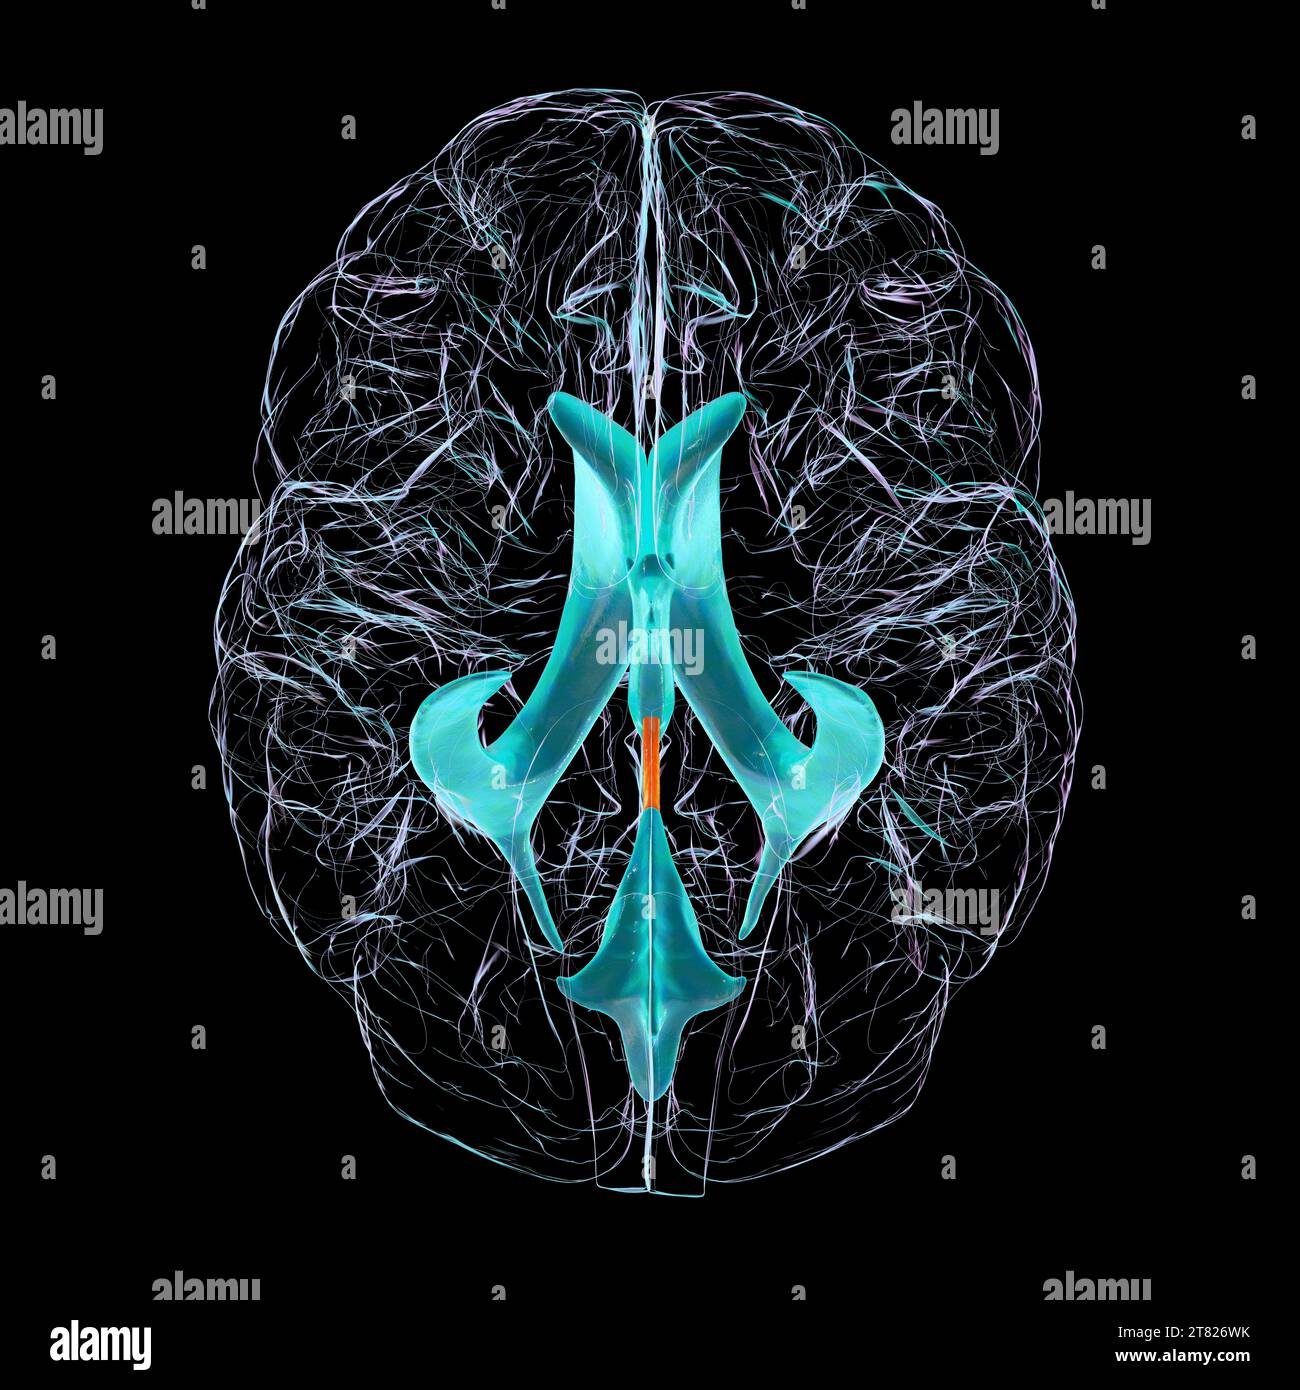

RF2T7NGWH–Ventrikel und zerebrales Aquädukt laterale Röntgenansicht 3D-Rendering-Illustration. Menschliches Gehirn und Ventrikelsystem Anatomie, Medizin, Gesundheitswesen, Scienc

RF2YX6R0N–Computerdarstellung des menschlichen Gehirns mit orangefarbenem Aquädukt und grünem Ventrikelsystem, die den Liquorfluss (CSF) zeigen.

RF2YX6R0K–Computerdarstellung des menschlichen Gehirns mit orangefarbenem Aquädukt und grünem Ventrikelsystem, die den Liquorfluss (CSF) zeigen.

RF2YX6R02–Computerdarstellung des menschlichen Gehirns mit orangefarbenem Aquädukt und grünem Ventrikelsystem, die den Liquorfluss (CSF) zeigen.

RF2YX6R05–Computerdarstellung des menschlichen Gehirns mit orangefarbenem Aquädukt und grünem Ventrikelsystem, die den Liquorfluss (CSF) zeigen.

RF2YX6R0G–Computerdarstellung des menschlichen Gehirns mit orangefarbenem Aquädukt und grünem Ventrikelsystem, die den Liquorfluss (CSF) zeigen.

RF2YYB746–Computerdarstellung des menschlichen Gehirns mit orangefarbenem Aquädukt und grünem Ventrikelsystem mit Liquorfluss.

RF2YYB74E–Computerdarstellung des menschlichen Gehirns mit orangefarbenem Aquädukt und grünem Ventrikelsystem mit Liquorfluss.

RF2YYB741–Computerdarstellung des menschlichen Gehirns mit orangefarbenem Aquädukt und grünem Ventrikelsystem mit Liquorfluss.

RF2YYB742–Computerdarstellung des menschlichen Gehirns mit orangefarbenem Aquädukt und grünem Ventrikelsystem mit Liquorfluss.

RF2YX6R0H–Computerdarstellung des menschlichen Gehirns mit orangefarbenem Aquädukt und grünem Ventrikelsystem, die den Liquorfluss (CSF) zeigen. Rückansicht.

RF2YX6R12–Computerdarstellung des menschlichen Gehirns mit orangefarbenem Aquädukt und grünem Ventrikelsystem, die den Liquorfluss (CSF) zeigen. Draufsicht.

RF2YYB740–Computerdarstellung des menschlichen Gehirns mit orangefarbenem Aquädukt und grünem Ventrikelsystem mit Liquorfluss. Rückansicht.